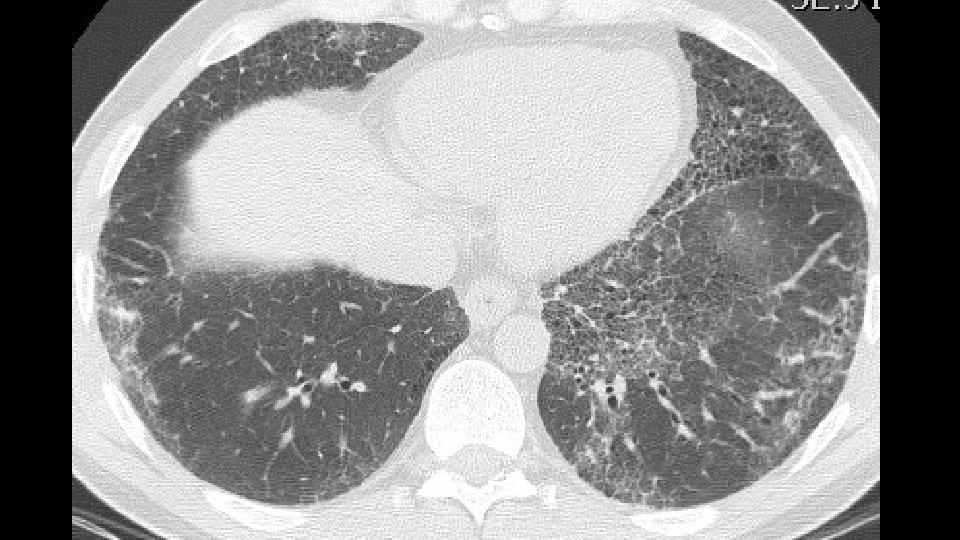

1. Mechanical stress and remodeling are highest in that areas in which traction bronchiectasis and honeycombing appear. Carloni A. et Al. Journal of theoretical biology 2013 2. Most of the "scarred" tissue is in the region distal to the traction bronchiectasis, beneath the pleura and does not concentrically surround the dilated bronchi. 2007 Score 1 bronchiectasis 2014 2010 Score 3 bronchiectasis Honeycombing

3. In Nonspecific Interstitial Pneumonia (NSIP), traction bronchiectasis are completely surrounded by the fibrotic tissue Fibrotic NSIPof the years NSIP in the course a 2009 b 2013